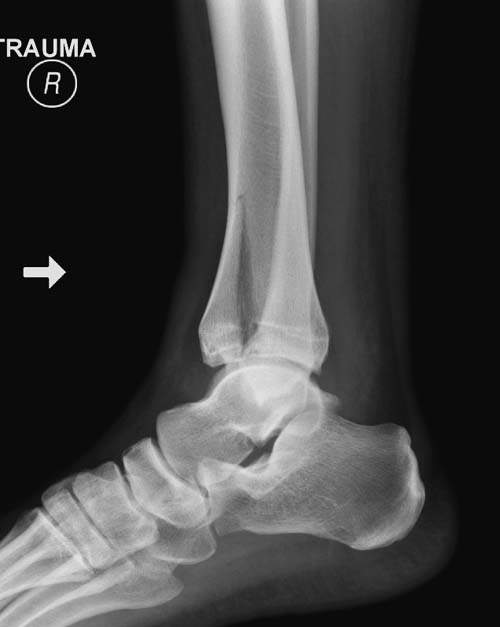

С ответом немного задержался, хотел подобрать материал, но трудно найти идентичный случай. На всякий случай подобрал пару, надеюсь, поможет.

Второй случай в результате скоростной травмы, кроме пилона, вовлечение других органов! Отек при поступлении и открытый перелом на другой стороне. В таких случаях нет смысла спешить, и временный наружный фиксатор на несколько дней. После спадения отека фиксация передне-наружной пластиной. Реабилитация - ранние движения, без нагрузки.